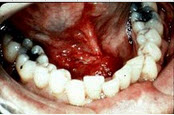

90、单项选择题

男,40岁,发现右侧口底部有一核桃大小质硬肿块(如图),触诊浸润已过中线。右侧颌下可扪及2个肿大淋巴结,黏连;左侧未扪及明显肿大淋巴结。关于颈部淋巴结的处理,以下哪项最佳()